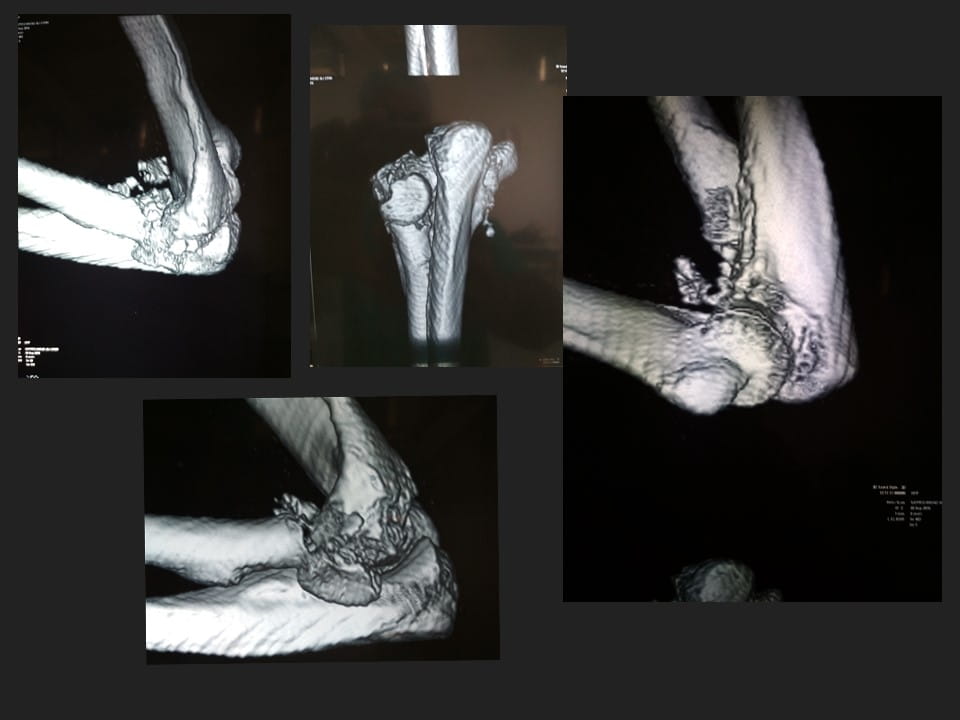

Terrible Triad